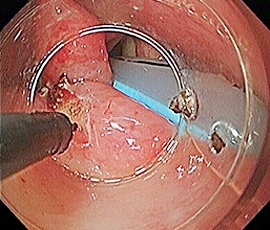

[咽頭腔外魚骨異物] 手術:内視鏡的粘膜下層剥離術(異物除去)

内視鏡画像